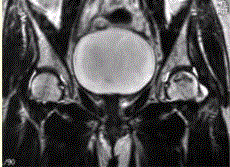

问题 患者男,47岁,左髋部疼痛及压痛6个月,“4”字试验阳性。左髋关节内、外旋活动受限。检查提示:左髋关节活动轻度受限,大腿上部轻压痛。血常规检查正常。髋关节CT及MRI如下图。 根据髋关节CT和MR影像,你认为此病例的影像学表现有

选项 A.CT检查未见异常 B.左侧股骨头内可见线样高密度影 C.左股骨头塌陷变扁,其内可见条带状硬化 D.左股骨头内见蜿蜒走行的T1、T2低信号条带影 E.左髋关节腔内可见弧线状长T1、长T2信号 F.左髋关节间隙变窄

答案 BDE